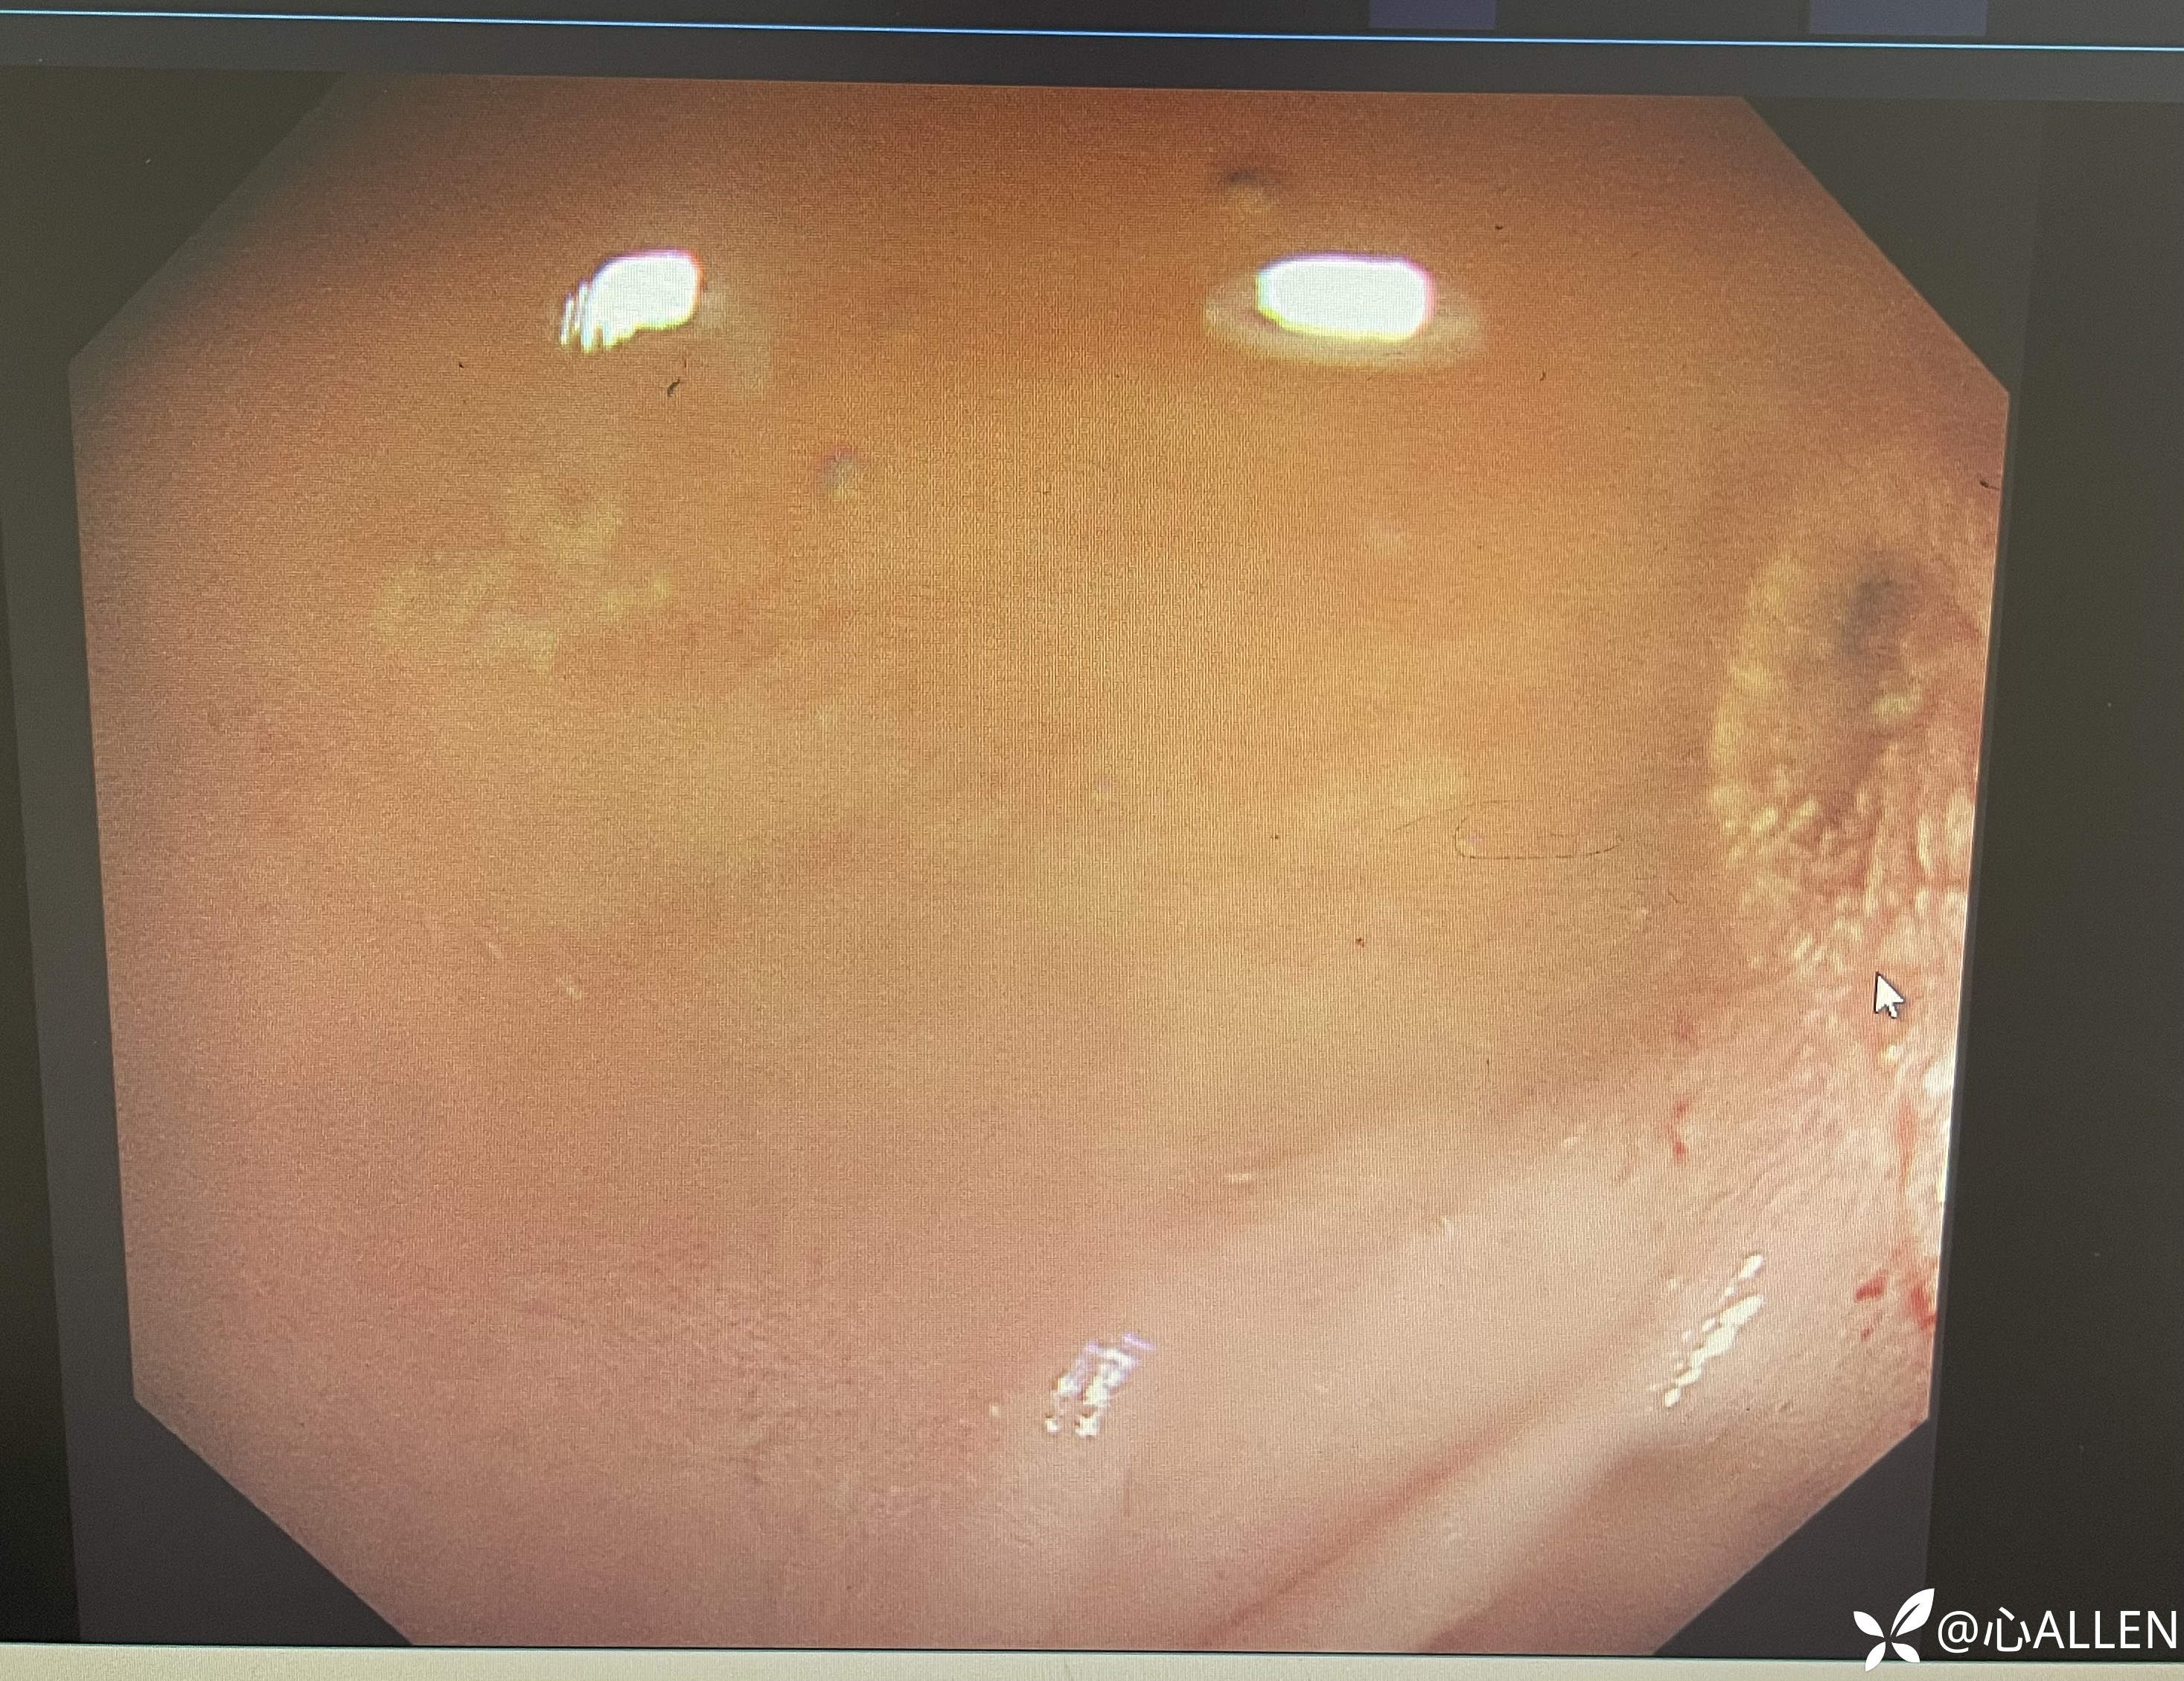

小肠黏膜正常,未见主乳头及分叉

退镜观察球部吻合口

球部吻合口黏膜正常